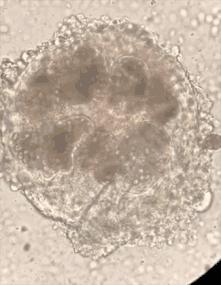

手术后,从京京胸腔、腹腔囊肿中抽取的囊液被送检。显微镜下,原头蚴清晰可见。

两个囊肿中抽取的寄生虫液,足足有1000多毫升!

做了充分的预案后,手术开始了。尽管有了心理准备,医生们还是“大开眼界”:从两个囊肿里抽取的囊液,竟然足足有1000多毫升!